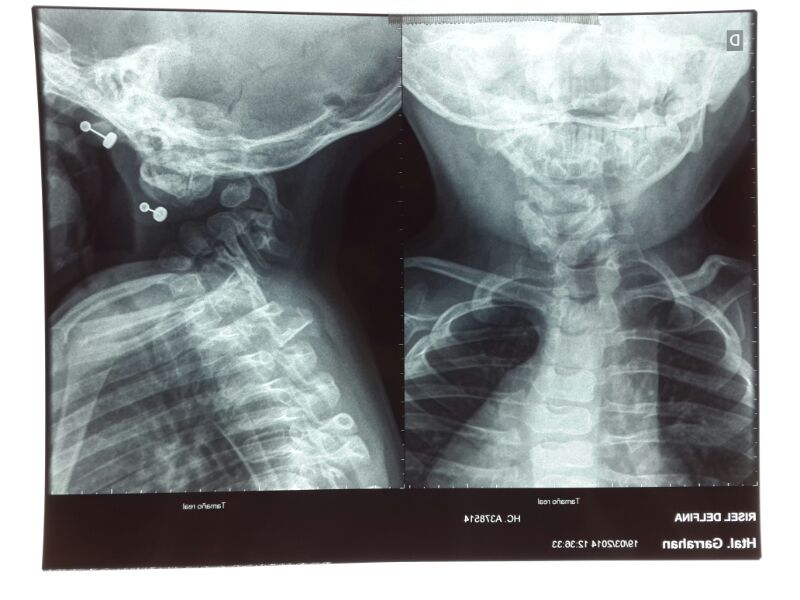

Instrumentación cervical en pacientes menores de 10 años. [Cervical Instrumentation and Fusion in Children Under 10 Years Old.]